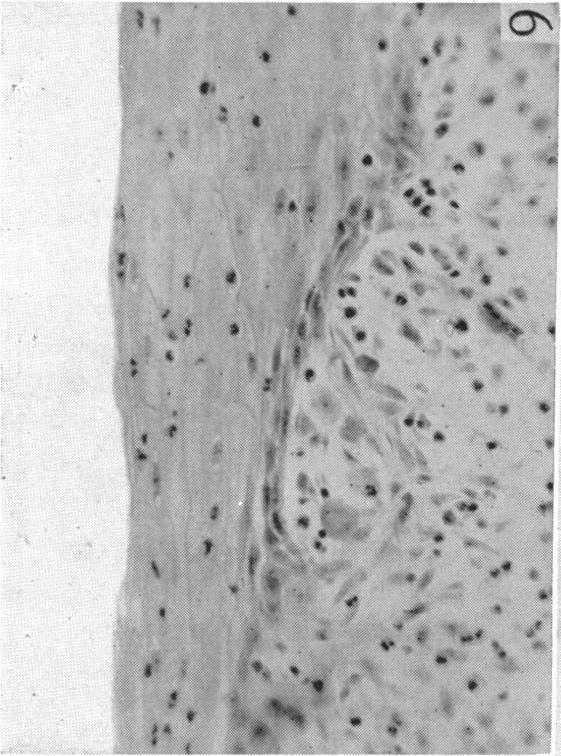

Gibson T, Medawar P B

Mr Clark's Surgical Unit, Glasgow Royal Infirmary.

J Anat. 1943 Jul;77(Pt 4):299-310.4.